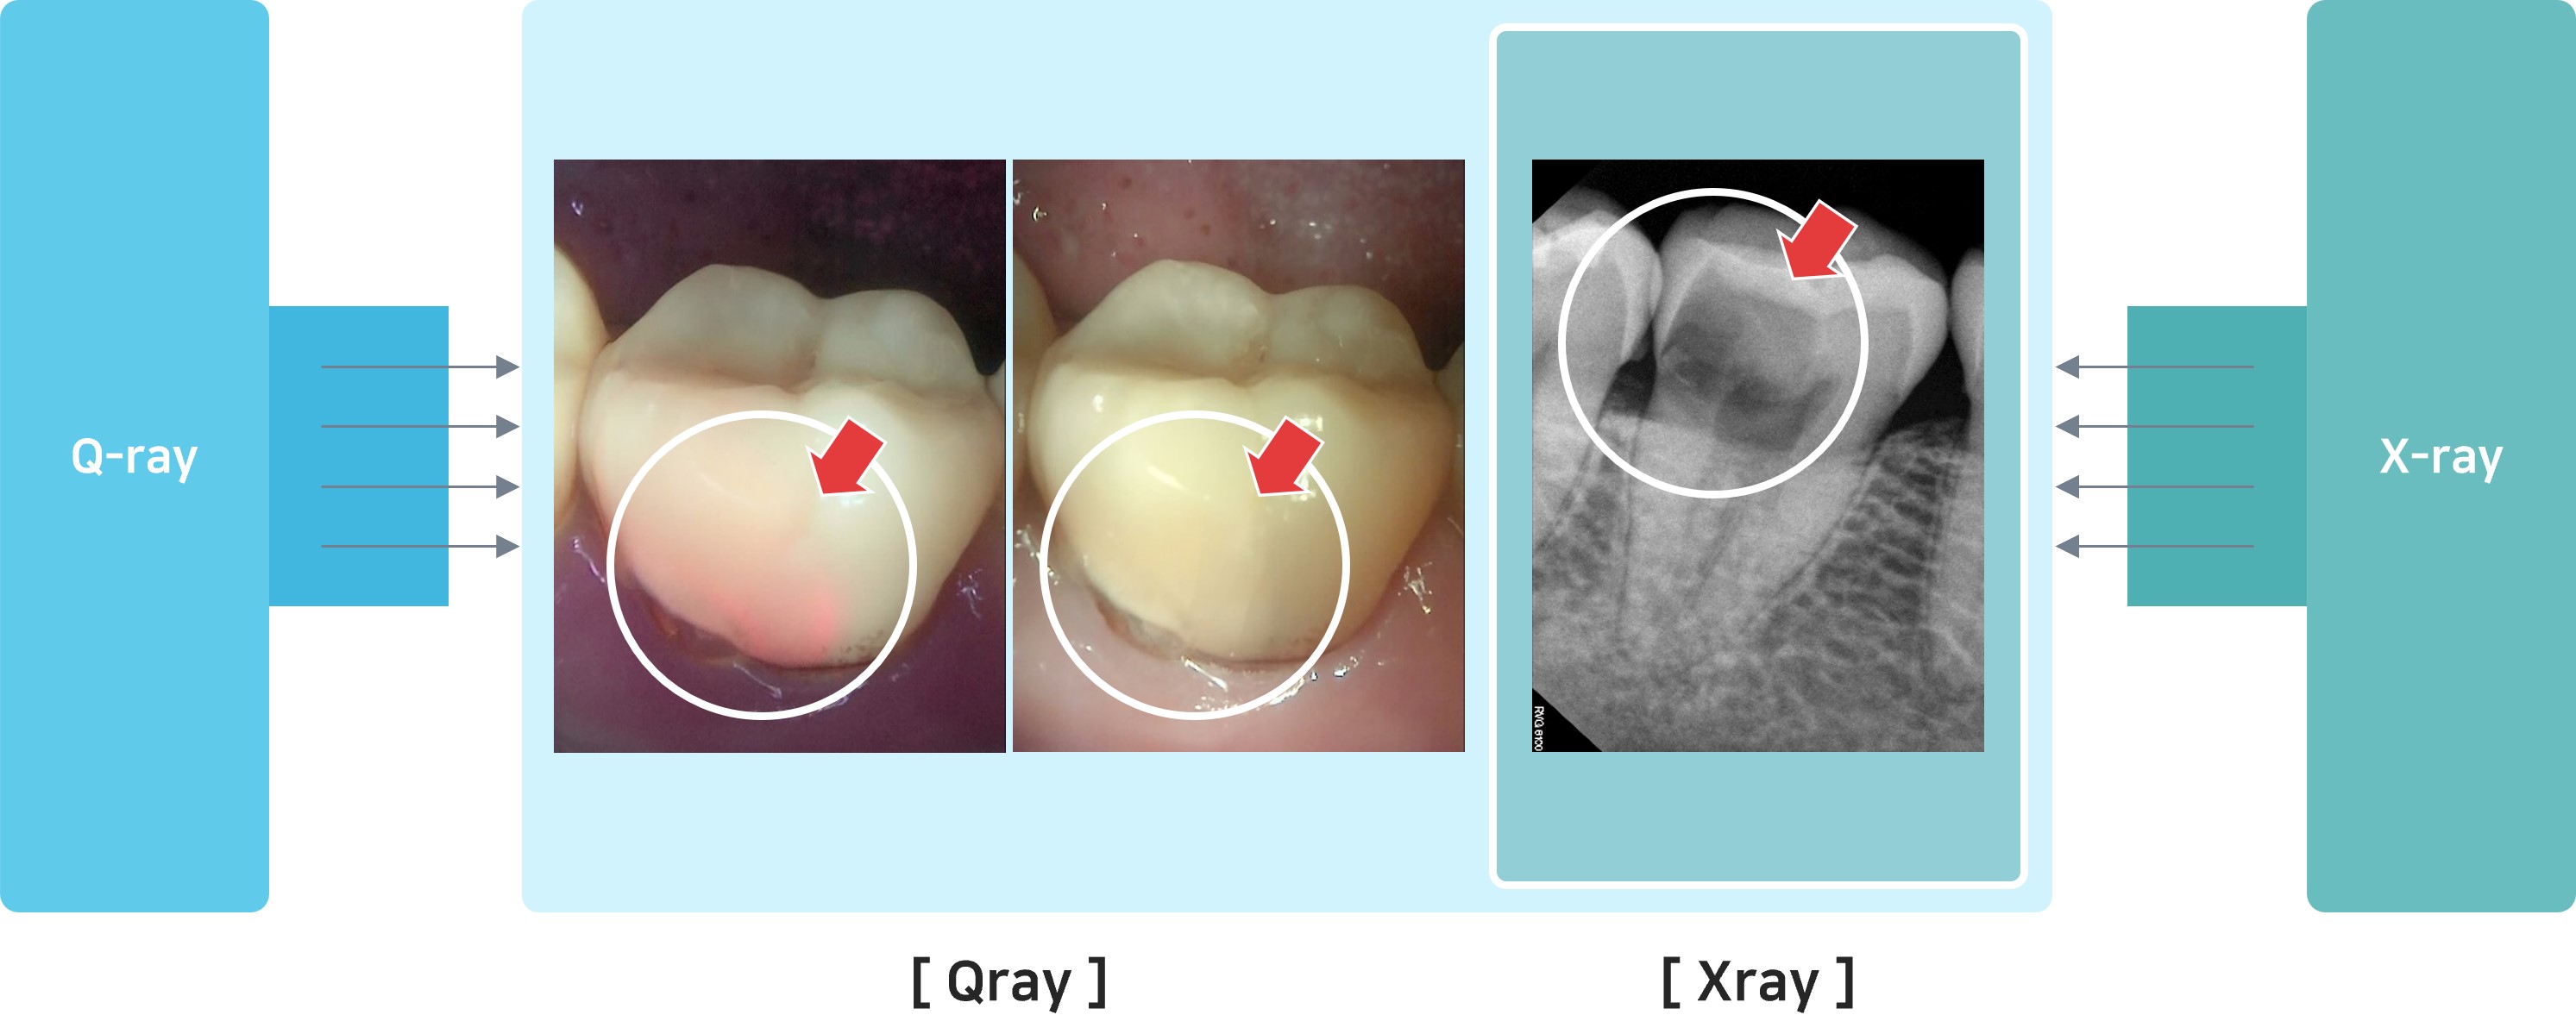

☞☞ 치과를 가시면 원장님들이 시진이라고 눈으로 입안을 검사하는 과정이 있습니다. 그 전에 큐레이라는 형광검사와 방사선검사를 시행하면 치아외부의 상태는 큐레이 사진이 보여주고, 파괴된 상태는 방사선 사진이 보여주게 됩니다. 보는 것이 믿는 것입니다. 치과에서 미래를 준비하시려면 '붉은형광, 큐레이' 입니다.